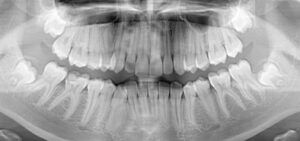

Konsultacja zawierała analizę cyfrowego planu leczenia oraz na dodatkowe zlecenie lekarza przeprowadzono jednocześnie pisemną analizę zdjęcia panoramicznego pacjenta.

Na dostarczonym zdjęciu panoramicznym widoczne były odmienne od standardowych kształty korzeni zębów 13 oraz 43. Wymagało to uwzględnienia do podjęcia modyfikacji pierwotnego planu leczenia (bazującego na statystycznych ruchach na zębach o anatomii nie odbiegającej od normy).

Cyfrowe plany leczenia obejmują ruchy i sekwencje ruchów zębów na bazie licznych analiz. W omawianym przypadku wnioski z analizy zdjęcia panoramicznego wpłynęły bezpośrednio na potrzebę modyfikacji pierwotnego planu leczenia. Zaproponowane na pierwszym planie leczenia ruchy konkretnych zębów wymagały zmiany ich zakresu, jak również sekwencji. Brak doświadczenia w leczeniu nakładkami może oznaczać brak skupienia na poszukiwaniu trudności anatomicznych jakimi są np. dłuższe niż statystyczne korzenie zębów, zmiany ich kształtów. Bez uwzględnienia modyfikacji planu leczenia, kliniczna ekspresja po wynoszeniu nakładek możliwe że nie satysfakcjonowała by lekarza.